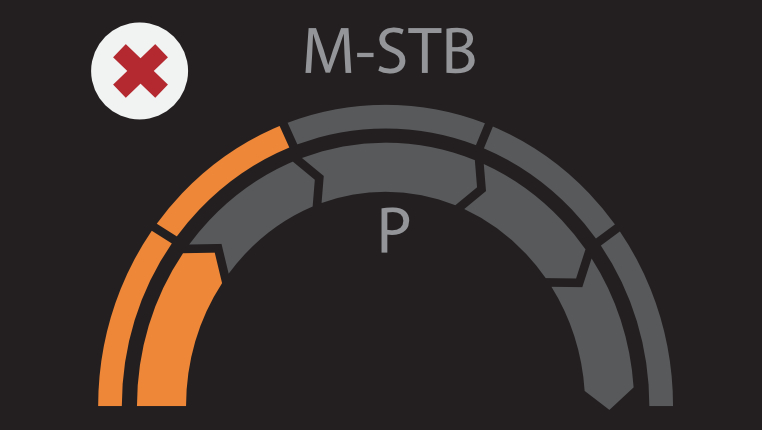

? ??? ?? ???? ???? ?? ???? Hepatus? ? ??? ??? ???? ??? ??? ?????. ???? ????? ??? ? ?? ??? ???? ????? ? ?? ???? ? ?? ??? ??? ??? ?????.

??? ???? ?? ? ??? ? ? ???? ?? ??, ??, ???? ? ?? ??? ??? ? ????. ?? ?? ???? ?????.